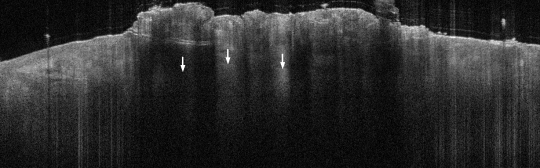

VA35: Left Temple, Actinic Keratosis, Hypertrophic

- White arrows indicate return to dermal collagen texture and reflectivity

VA35: Left Temple, Adjacent, Normal